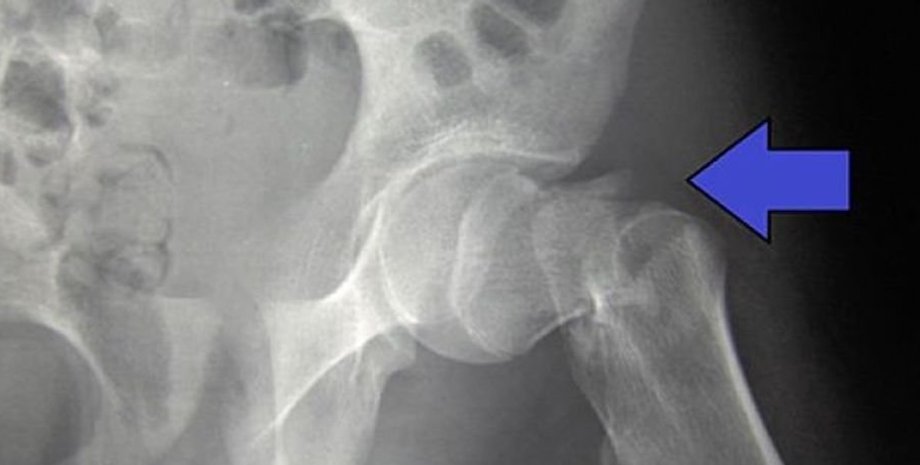

Только на переломы бедра приходится 1,8 миллиона койко-дней и 1,1 миллиарда фунтов стерлингов на больничные расходы каждый год, не считая высокой стоимости социальной помощи. Цель исследования состояла в том, чтобы выяснить, могут ли механические вибрации улучшить то, как наши тела обрабатывают и реагируют на небольшие колебания тела.